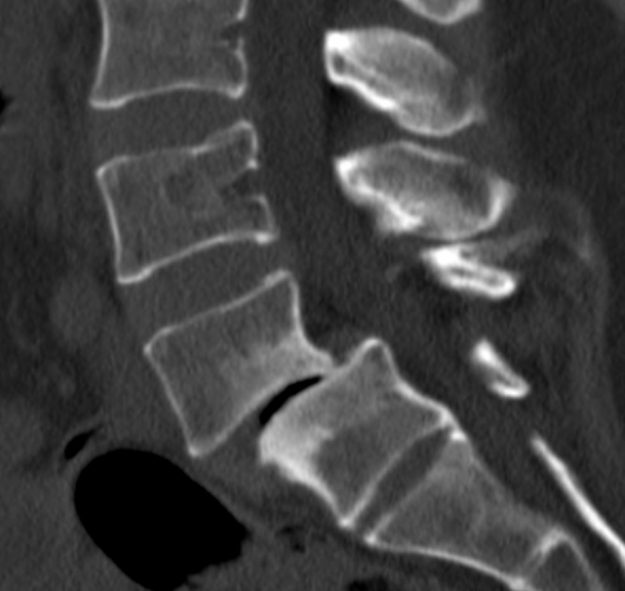

Μετάσταση 10ου Θωρακικού Σπονδύλου (Θ10)

Ασθενής άνδρας 72 ετών με έντονη ραχιαλγία και ιστορικό καρκίνου του πνεύμονα. Ο απεικονιστικός έλεγχος με μαγνητική και αξονική τομογραφία της σπονδυλικής στήλης ανέδειξε μάζα κυρίως στο σώμα του 10ου θωρακικού σπονδύλου (Θ10) με περιβρογχισμό και πίεση επί του νωτιαίου μυελού. (Σημειώστε και τη διήθηση του Θ9 σπονδύλου, χωρίς οστεόλυση). Διενεργήθη αποσυμπίεση του νωτιαίου μυελού…